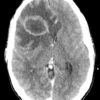

Apxe não

» Thông tin: Nam giới – 35 tuổi.

» Lâm sàng: Đau đầu.